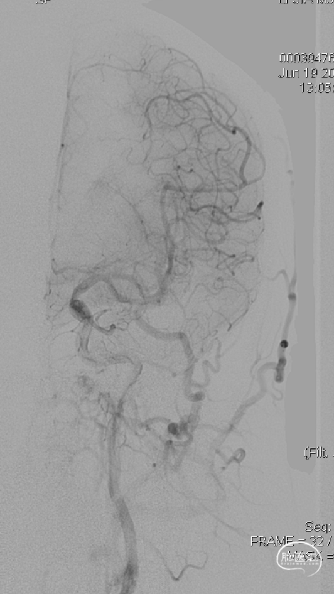

LECA

左侧咽升供血的HCDAVF,逆流至海绵窦,经眼上静脉-面静脉引流。